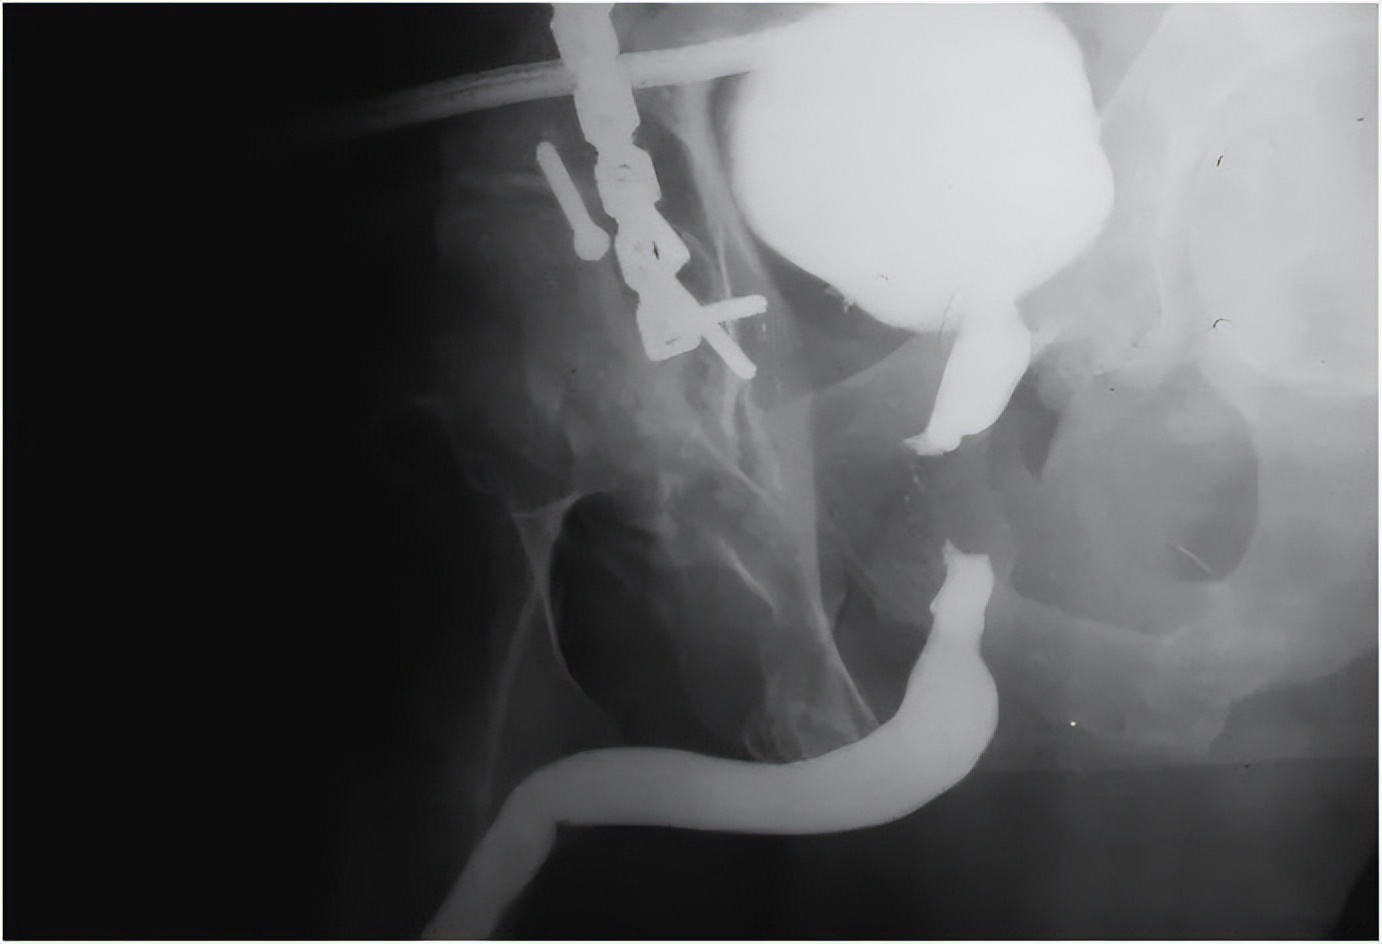

骨盆骨折导致的创伤性尿道狭窄尿道造影图像